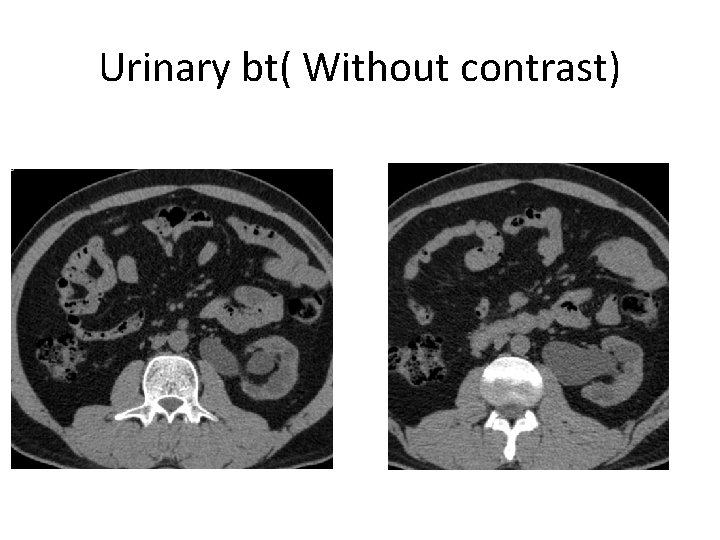

Urinary bt( Without contrast)

US • Solitery enlarged left kidney and proximal segments of ureter

• PTH 354 pg/ml • Uric acid 8. 9 mg/dl • Culture of urine : (-) What is your likely diagnosis ?

Nephropathy of VUR